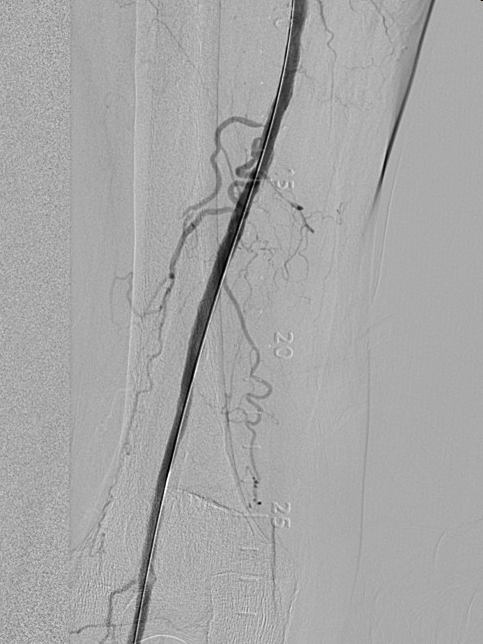

图1

股动脉下段闭塞,

图1为术前DSA,图2为术后DSA